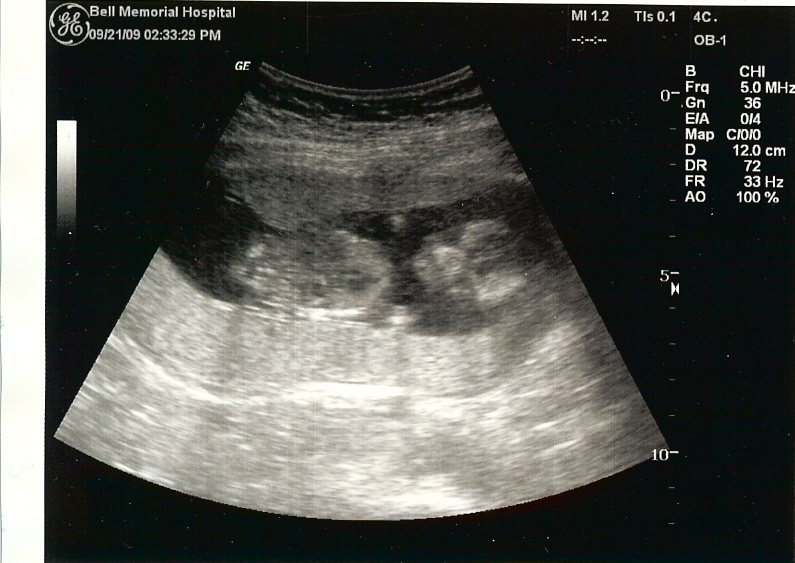

Hi, my name is Samuel Ezra Salo! I was in my Mommy's tummy for quite awhile. I got out of her tummy on March 17, 2010 at 4:54pm. (I didn't have my watch on so I cannot confirm the time.) Daddy and Mommy tell others I was 10 pounds 3 ounces and was 21 1/2 inches long when I came out of my Mommy's tummy. I don't know what that means but will probably figure out someday. For now I will just hang out with Daddy and Mommy.